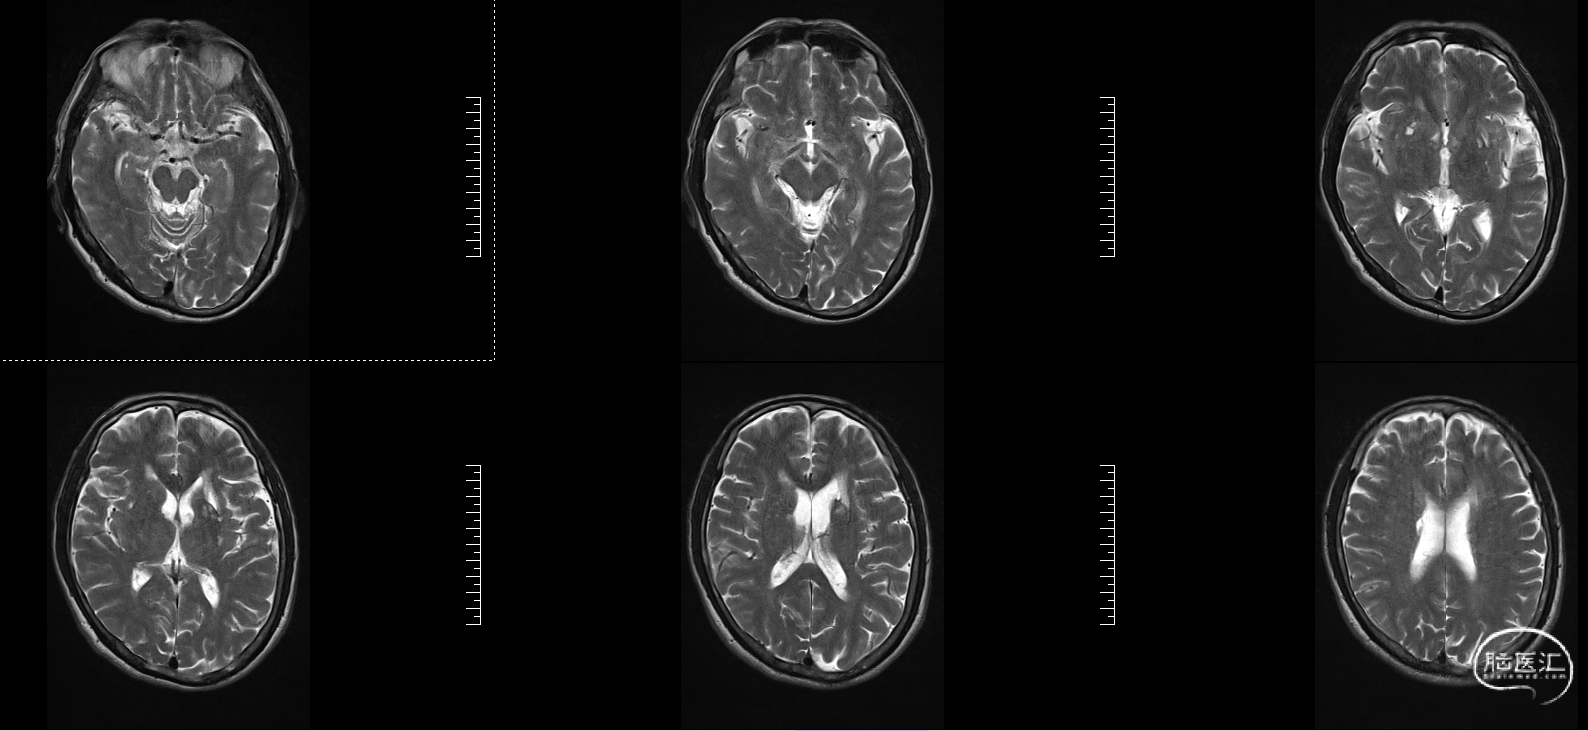

头颅MRI:左侧额顶叶急性脑梗塞;桥脑左份、双侧基底节、右侧脑室旁及双侧额叶多发腔隙性脑梗塞;双侧脑室旁及额顶叶轻度白质脱髓鞘;双侧上颌窦、筛窦、蝶窦炎;脑MRA示①右侧椎动脉纤细(变异)②左侧大脑后动脉P2段局部狭窄③左侧颈内动脉眼段局部严重狭窄④脑动脉轻度硬化改变,请结合临床及其他检查协诊。

溶栓同时急查头颅磁共振T2

2、MRI提示:左侧额顶叶急性脑梗塞。